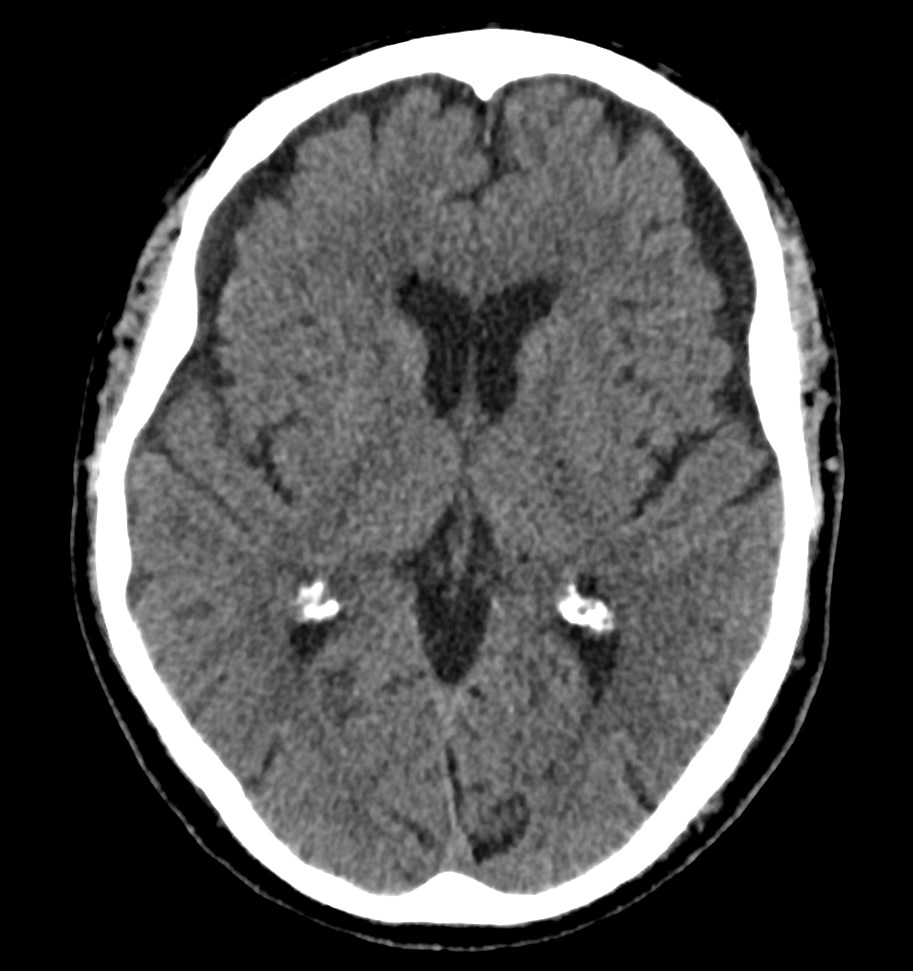

TAC cráneo: Hematoma subdural subagudo-crónico y efecto compresivo con obliteración de surcos frontoparietales.

Último TAC de control: Resolución del HSD derecho.